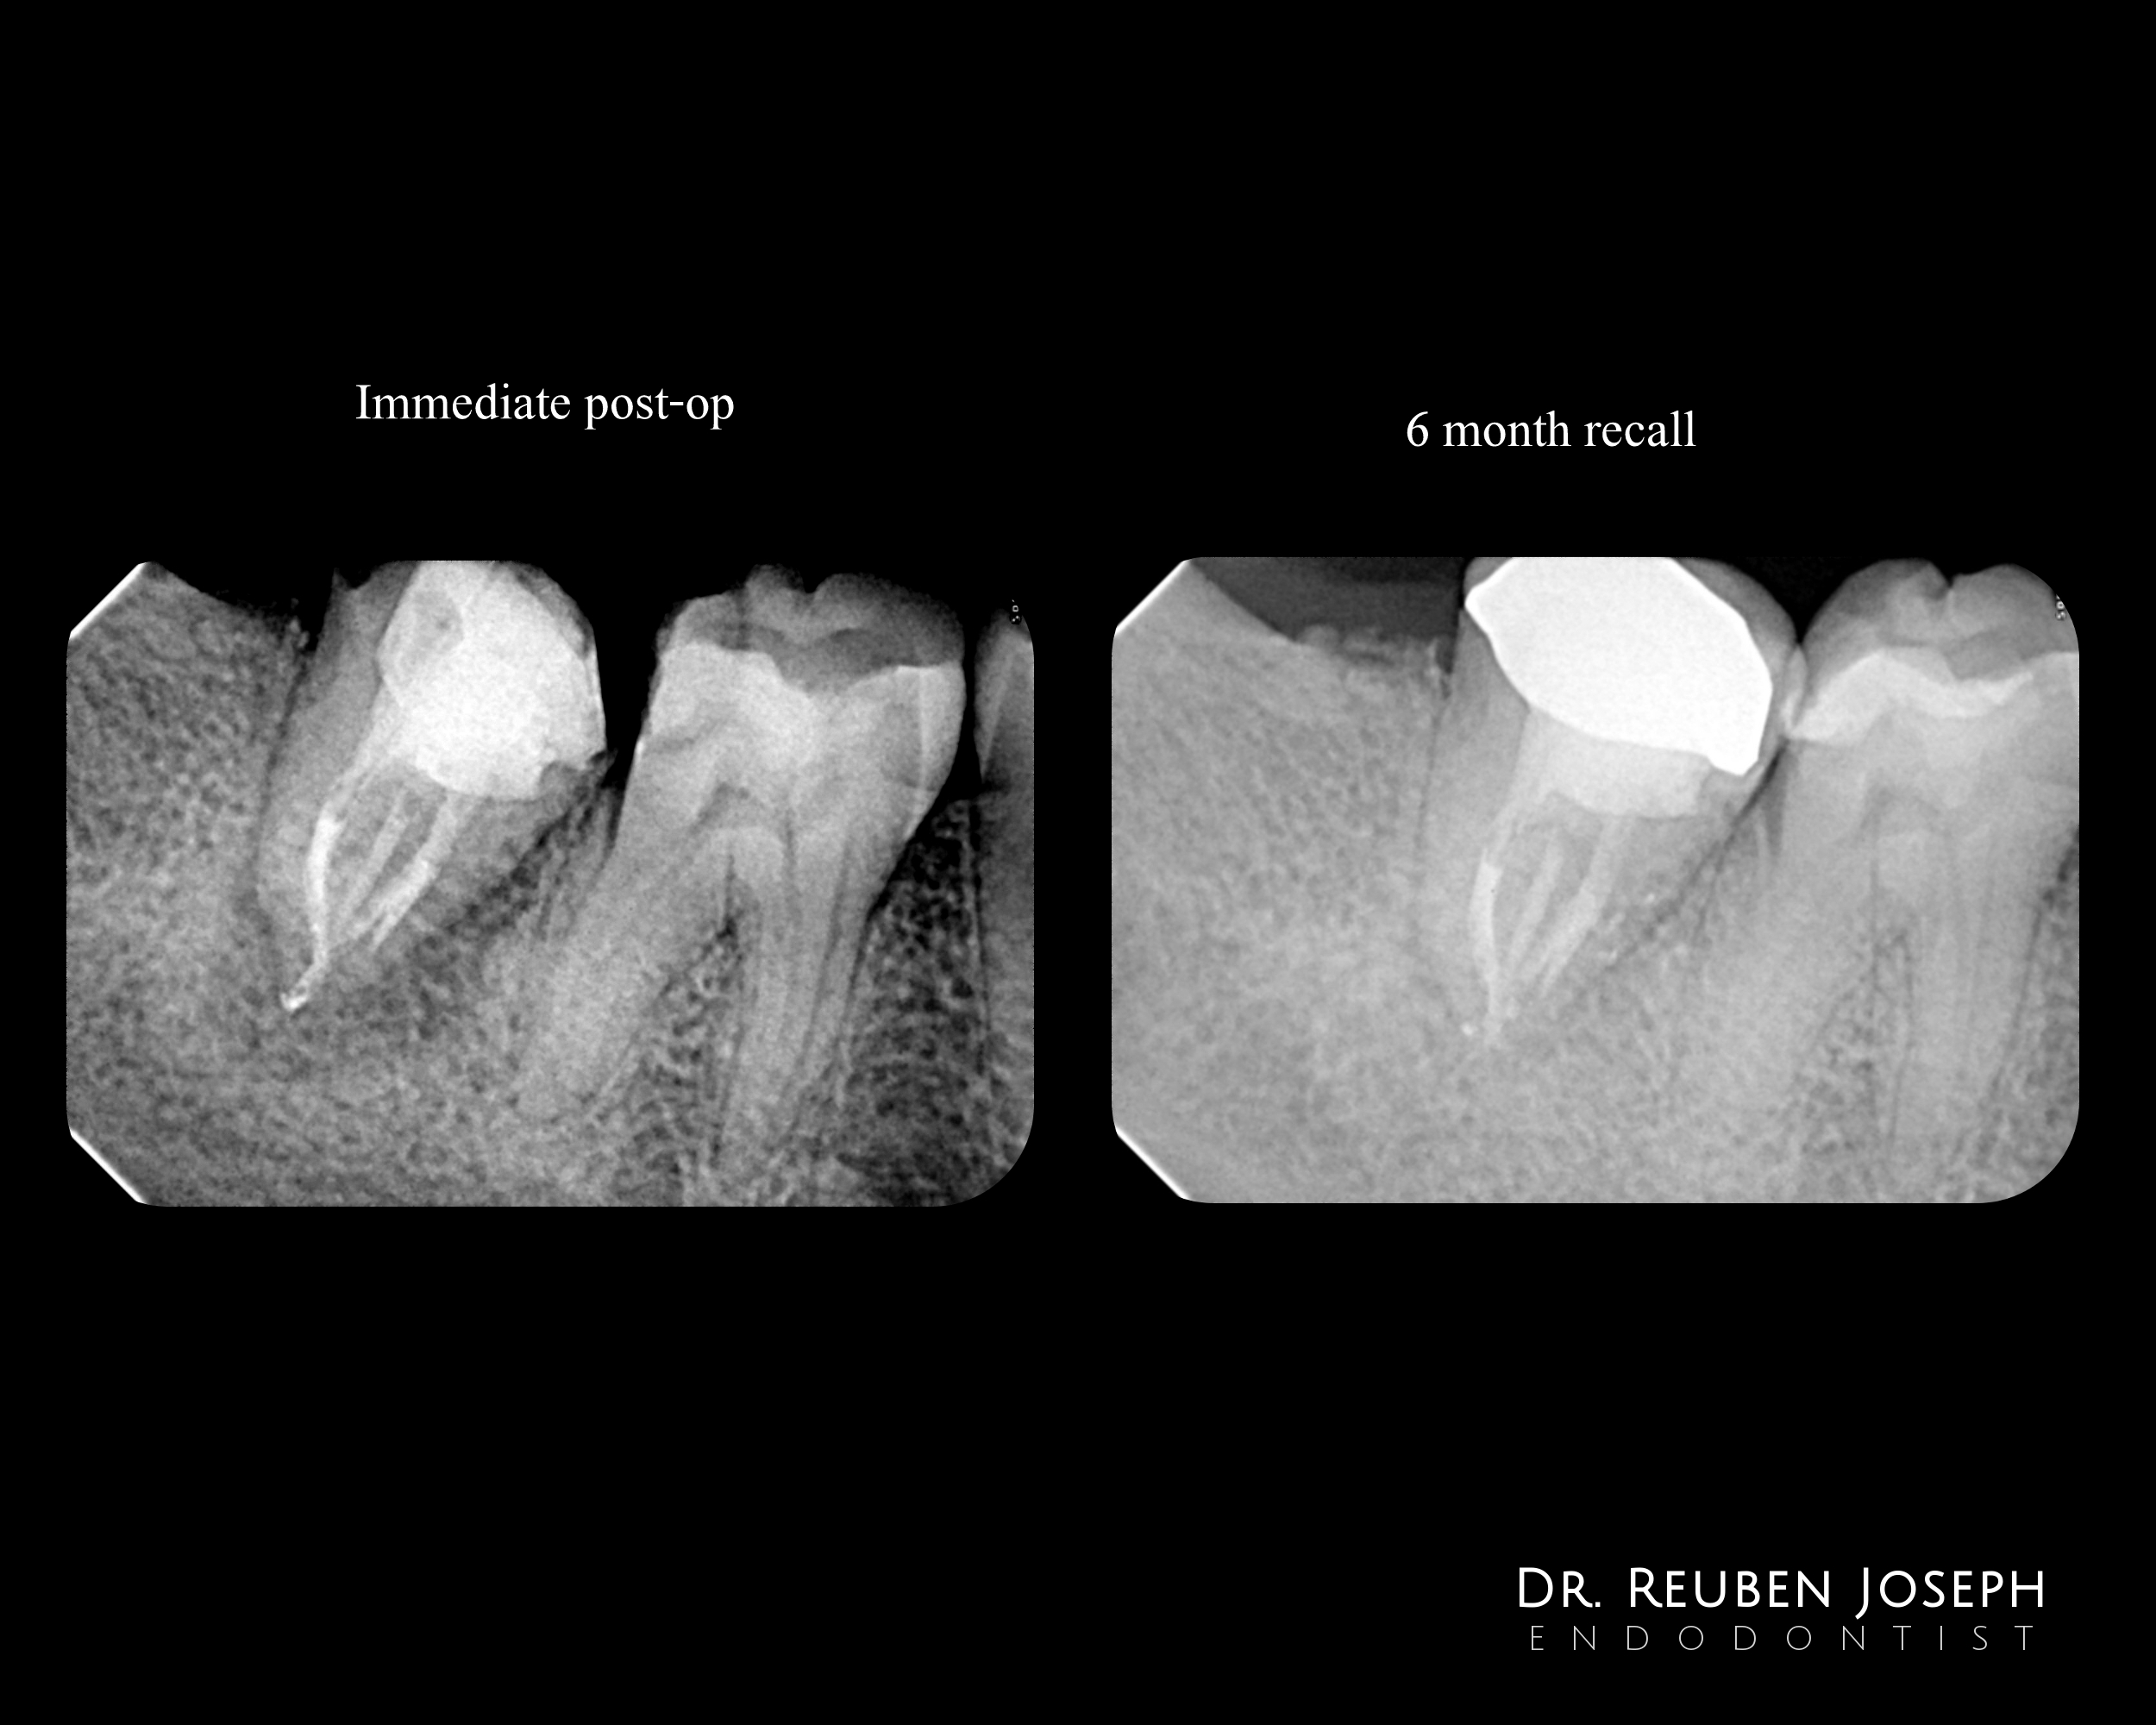

1st Visit

Exploratory access to assess prognosis to confirm restorability and rule out fracture

2nd visit

– GP removed and 2 of the 3 canals shaped

– Canals confluent

– File retrieved from the 3rd canal with U-file

– CaOH dressing given

3rd visit

Draining sinus had healed, shaped and obturated. 2 posts passively cemented

Review

Signs of good healing

I think this is a very nicely managed case and it is always nice to see specialists make the extra effort to bring difficult cases around and not quit just because they are difficult.

Having said that, my own experience with C-shaped lower molar re-treatments, is that when you look at them 10 years later, many of them are gone. I don’t know why, or if it is the C-shape that is particularly problematical, but whatever the reason(s), they haven’t stood the test of time—at least in my practice.

Thank you for your inputs Dr Gary. I haven’t been doing root canals that long, maybe I would get a similar end result in time with my C shapes as well. I think it’s mainly the thin Dentin and the periodontal compromise a fused root comes with. Thanks again for your input and time 🙂